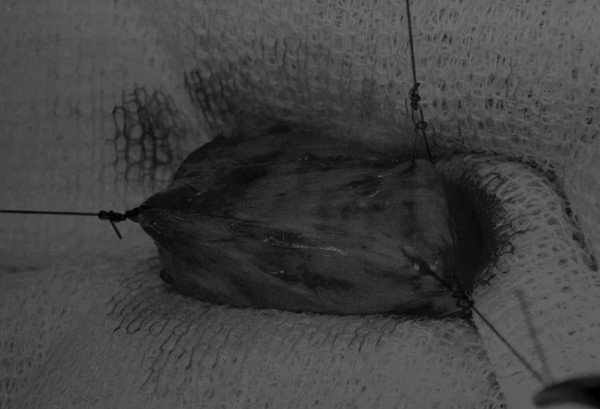

手术方法 在中线开腹手术后,确定膀胱,将其取出并隔离(图1)。为了使膀胱持续暴露,可在膀胱中线两侧各放置一根固定缝线(图2)。 在切开膀胱前,应用膀胱穿刺的方法获取尿液样本进行微生物培养。 图2 在手术过程中,还需要另外两根固定缝线来保持膀胱切开术的膀胱边缘处于暴露状态 在牵引缝线之间选择血管扩张较差的区域用手术刀切开膀胱壁(图3)。在牵引缝合线之间用手术刀在血管不良的区域做切口。切开膀胱壁后,膀胱内的手术可按手术方案实施,例如取出结石(图4)。 图3 避开主要的膀胱血管,做一个尽可能小的切口 切口可以在膀胱背侧或腹侧进行,避免对大血管的损伤。 图4 这张图显示了从膀胱中取出的大量结石 完成膀胱内冲洗后,应通过导尿管反向冲洗膀胱;砂样结石和血块会被冲到切口表面(图5) 图5 通过导尿管注入无菌生理盐水反向冲洗,可以去除微小的结石(箭头)和夹杂在膀胱黏膜皱褶中的砂样结石,以及可能在手术中形成的血块 膀胱创面采用单丝合成可吸收缝线缝合,采用外科医生习惯的缝合方式,但注意不要刺穿黏膜层(图6、图7)。 图6 使用简单的连续缝合。尽量不要用针刺穿黏膜层(箭头),以免缝线与尿液接触 图7 缝线应带入足够的切口两侧的膀胱组织,以确保在膀胱充盈时,没有伤口裂开 图8 这张图显示了通过导尿管注射的盐水,在缝合的切口处没有液体渗漏 关膀胱后,将无菌盐水注入膀胱腔内,检查是否有渗漏(图8)。 膀胱切开术闭合创口后,冲洗腹腔,以清除可能进入腹腔中的任何尿液、沙样结石或血凝块。 然后膀胱上覆盖小片的网膜,开腹手术伤口以通常的方式闭合。 手术视频 长按识别二维码观看视频